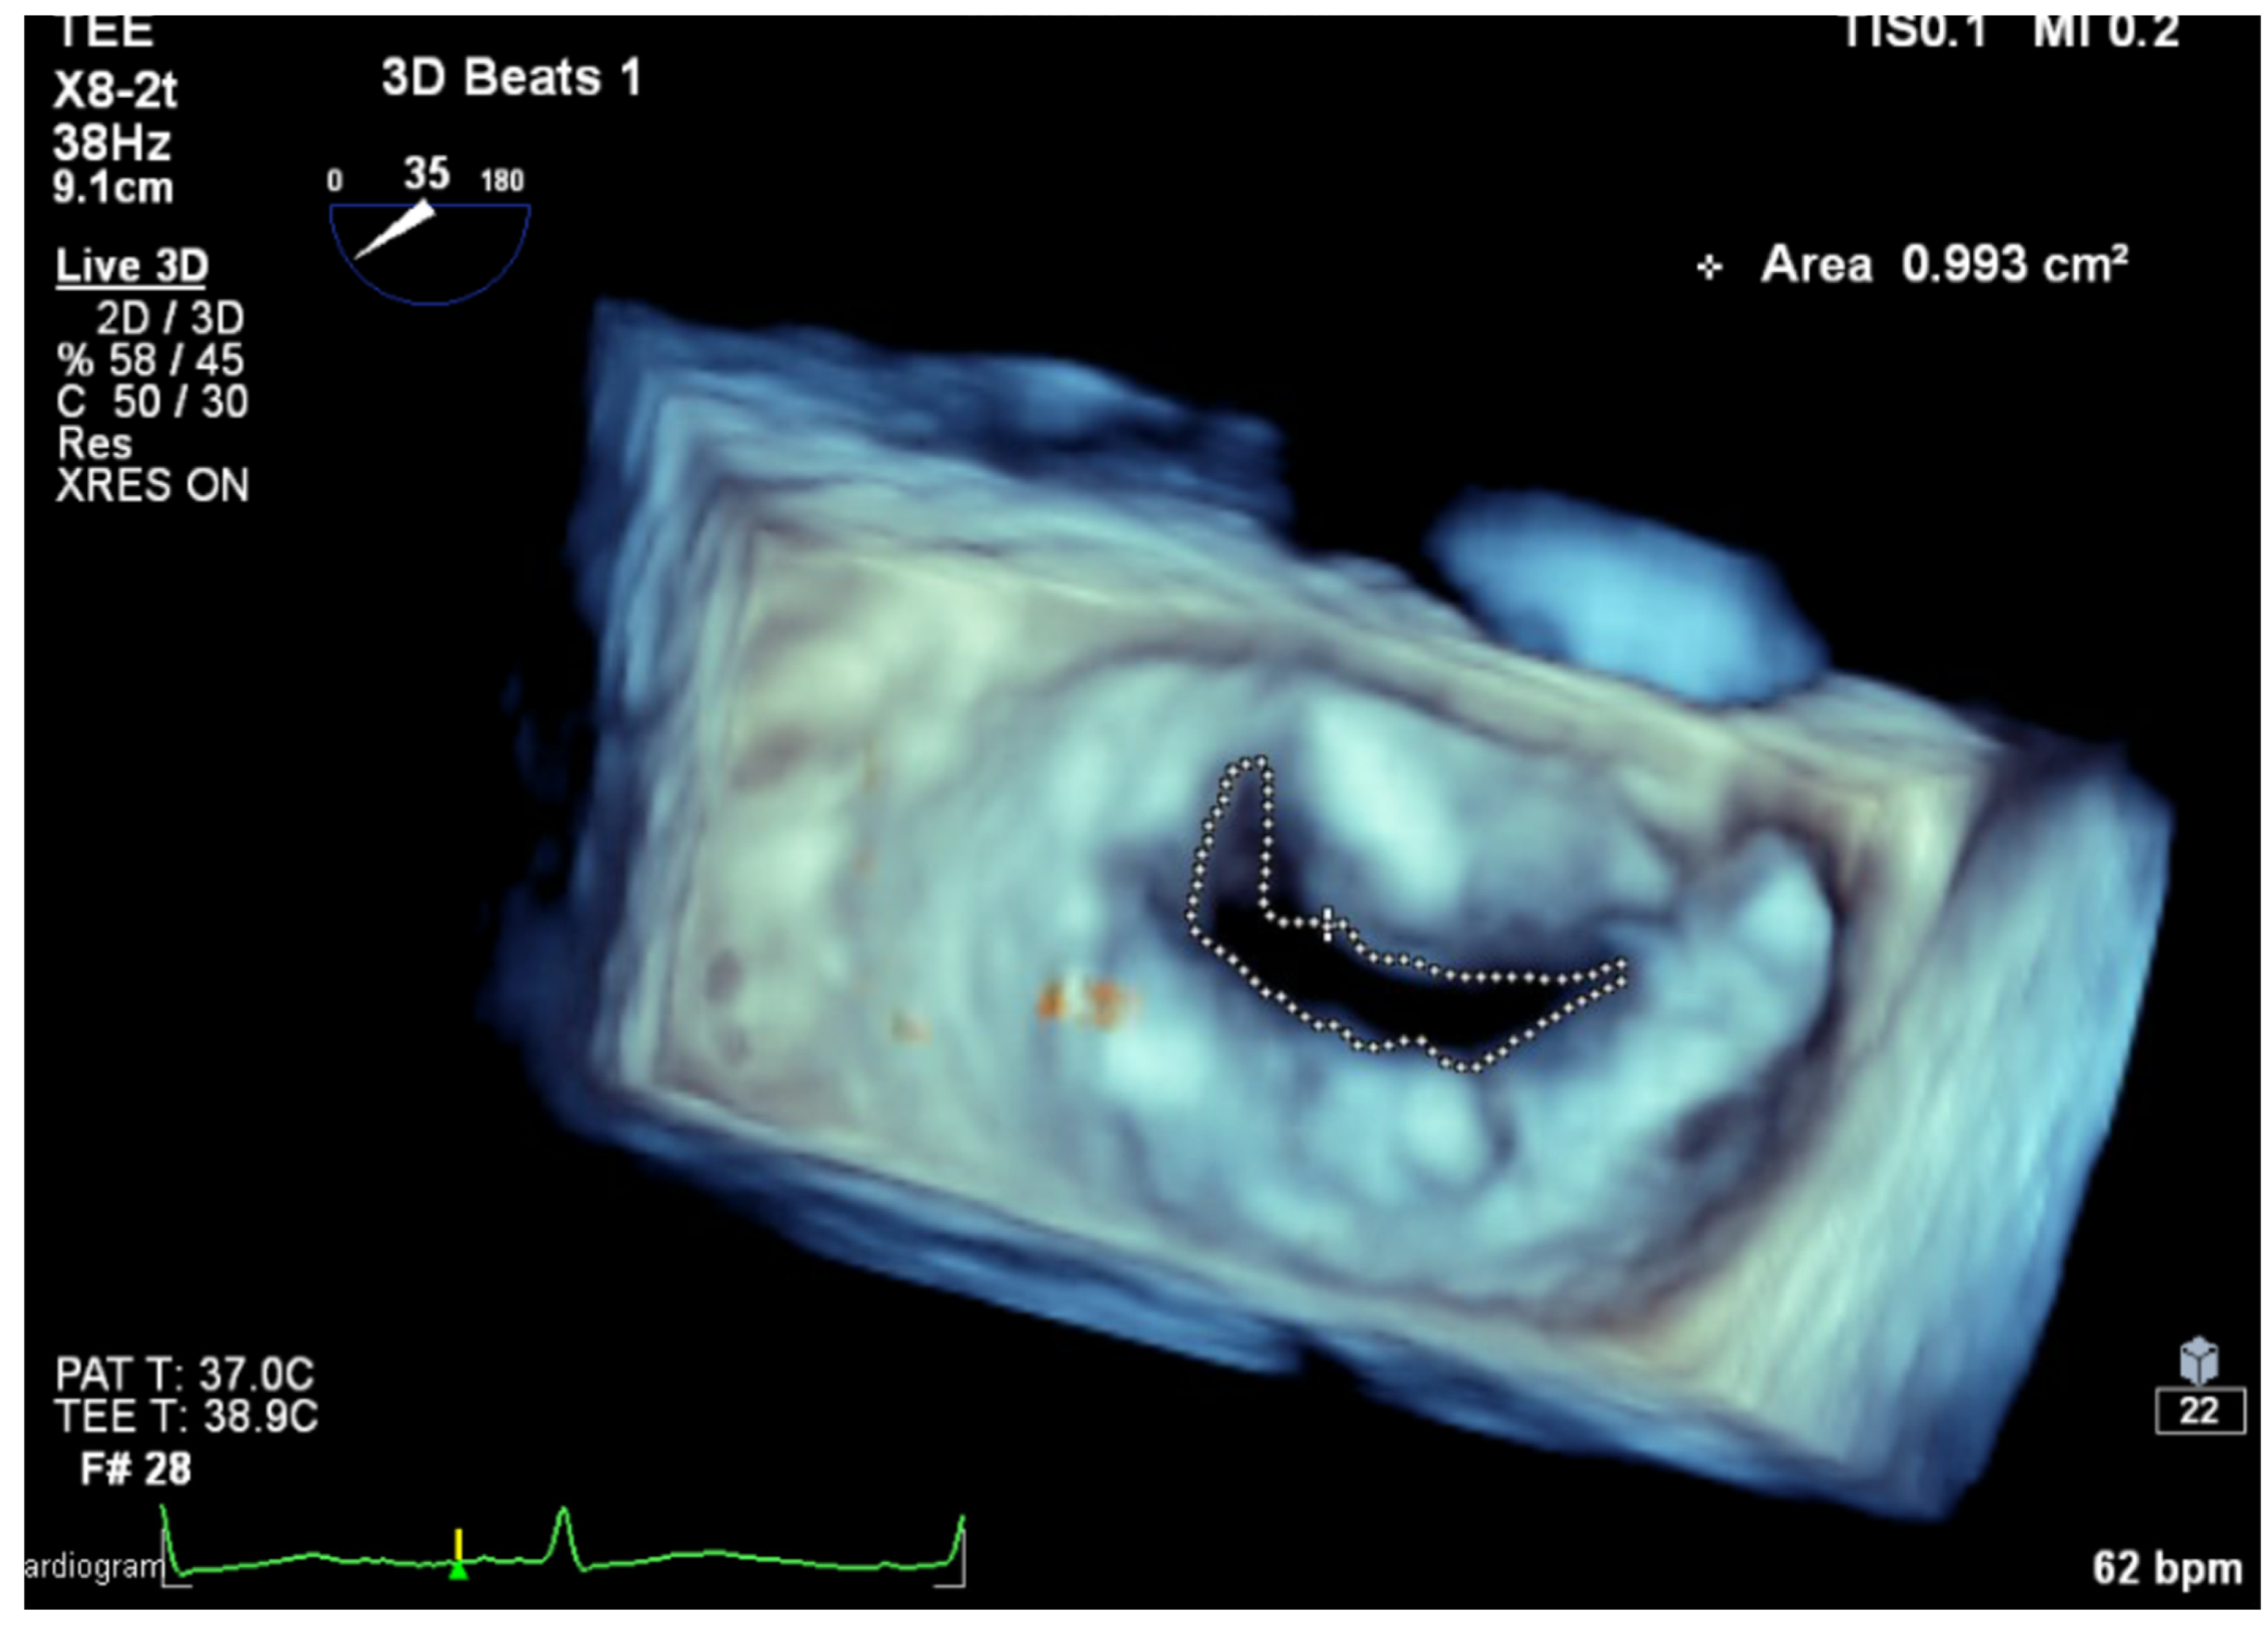

Planimetry by 2D echocardiography accurately evaluates the severity of RMS [41], where the mitral valve typically presents as a funnel shape, allowing for precise measurement at the leaflet tips. In contrast, the tubular and non-planar geometry seen in MAC-related MS thwarts the accuracy of planimetry by 2D echocardiography. Planimetry by three-dimensional (3D) echocardiography is as accurate as volumetric assessment of MAC-related MS independent of MR or AI [42] (see Table 1 and Figure 6). In patients with MAC-related MVD, the role of MDCT is limited to MV anatomy and planimetry of MV area.

Figure 6.

MVA measurement using 3D TEE planimetry. (MVA: mitral valve area, 3D TEE: three-dimensional transesophageal echocardiography).